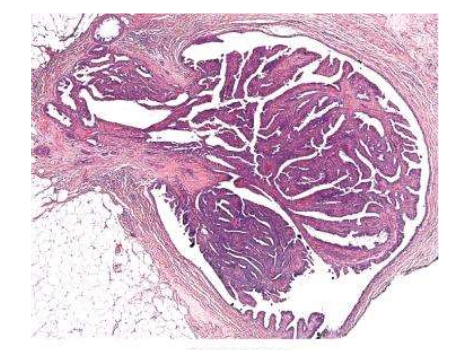

papilloma histo

branching fibrovascular cores within a duct

epithelial hyperplasia often present (more than 2 layers)